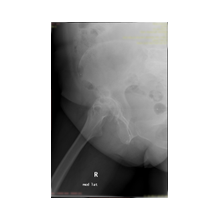

Kalça Protezi

Peki kalça protezi ameliyatın da neler yapıyoruz? Diz protezi ameliyatındaki benzer aşamaları uyguluyoruz. Kalça eklemi dize göre yapısal olarak ve çalışma sistemi olarak farklıdır. Kalça eklemi bir yuva ve onun içinde hareket eden femur başı dediğimiz bir toptan oluşur. Kalça eklemi kireçlenmesinde bu baş ve yuva yüzeyindeki kıkırdakların aşınması sonucu başın yuvarlaklığı kaybolur, sonuçta ağrı ve hareket kısıtlılığı ortaya çıkar. Bu yüzeyleri değiştirirken öncelikle bu başı kesip atıyoruz. Daha sonra yuvayı yine kılavuzlarla oyup uygun büyüklükteki protezi sıkıştırdıktan sonra en az 2 vida ile kemiğe adapte ediyoruz. Daha sonra alt uyluk kemiğini yine kılavuzlar yardımı ile oyduktan sonra kemiğe adapte ediyoruz ve sistemi birleştiriyoruz.

Görüntüleri büyütmek için üzerine tıklayınız.